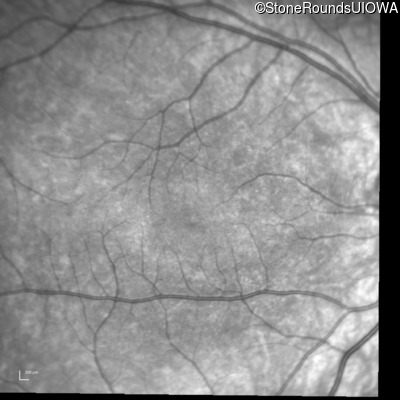

Infrared Fundus Photograph - Right - 10/160 +1 sc

Exemplar